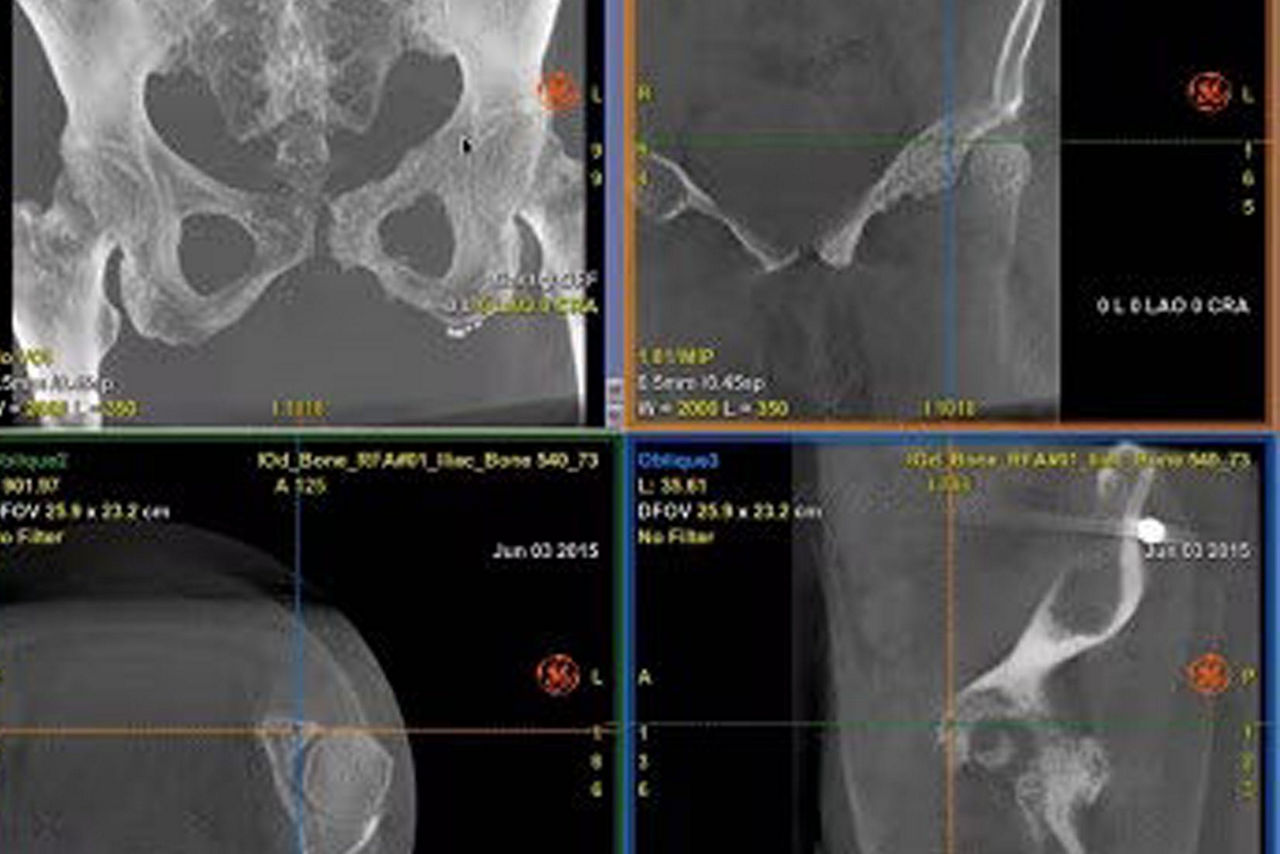

Real-time visualization

Provide real-time visualization of needle positions in the 3D space